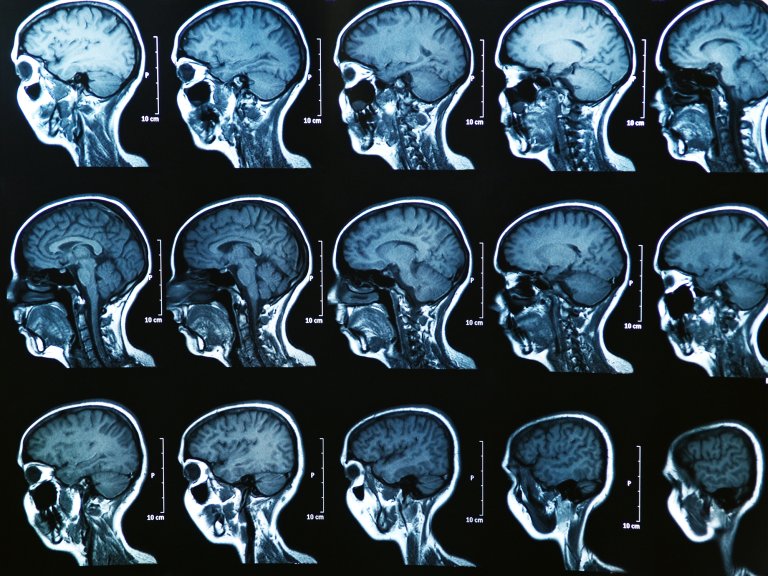

Your brain is unwell

MC Wolfman illustration

Something’s wrong up there. MC Wolfman

Ghostly occurrences can be the result of larger problems in our gray matter. For some, hearing voices or experiencing a vision can be an early indicator of medical conditions such as schizophrenia. Some evidence even suggests that people with underlying brain disorders tend to have paranormal confrontations that are more intense and negative than the average brush with the beyond.

Even in those without mental illness, temporary changes in brain activity can lead to run-ins with wraiths. People who experiment with psychoactive drugs like LSD and magic mushrooms frequently report spiritual fantasies. Furthermore, psychiatrists have deemed many visions the result of sleep paralysis, a poorly understood condition in which the afflicted wake up and find themselves unable to move. Scientists have yet to pinpoint the roots of this phenomenon, but some think it occurs when the brain crosses wires between conscious awareness and the dream-filled REM stage of slumber. This mixup is almost always accompanied by a sensation of entrapment, floating, or detachment from one’s body—and in many cases sleepers see an accompanying demon or hag. According to a 2018 survey in the International Journal of Applied and Basic Medical Research, at least 8 percent of the general population and around 30 percent of people with psychiatric illnesses have reported having one of these nighttime episodes at some point in their lives. Many cultures even have a specific name for the ghoulish occurrence. In Cambodia, for instance, the freakish event is called “the ghost that pushes you down”; in Nigeria, meanwhile, locals have another name for it: “the devil on your back.”